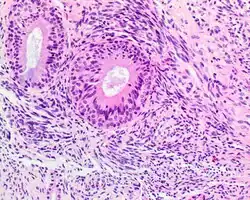

A high-power view of a hematoxylin- and eosin-stained slide showing respiratory epithelial inclusions within a spindled cell neoplasm showing characteristics of a biphenotypic sinonasal sarcoma

• Infiltrative, highly cellular spindled cell neoplasm is poorly circumscribed and unencapsulated. Bone destruction or invasion is common. The cells show medium to long fascicles (nerve fibers), with a herringbone pattern. The cells are remarkably uniform with elongated nuclei. Delicate strands of intercellular collagen without ropy or dense deposition are seen. A very characteristic concurrent surface-type respiratory epithelial proliferation is found from the surface or in small cystic spaces around the cancer cells, often forming glands. The background may have a rich vascularity and usually has a small number of scattered lymphocytes. Extra growths or mitoses are rare, while necrosis, ulceration, and hemorrhage are usually absent.